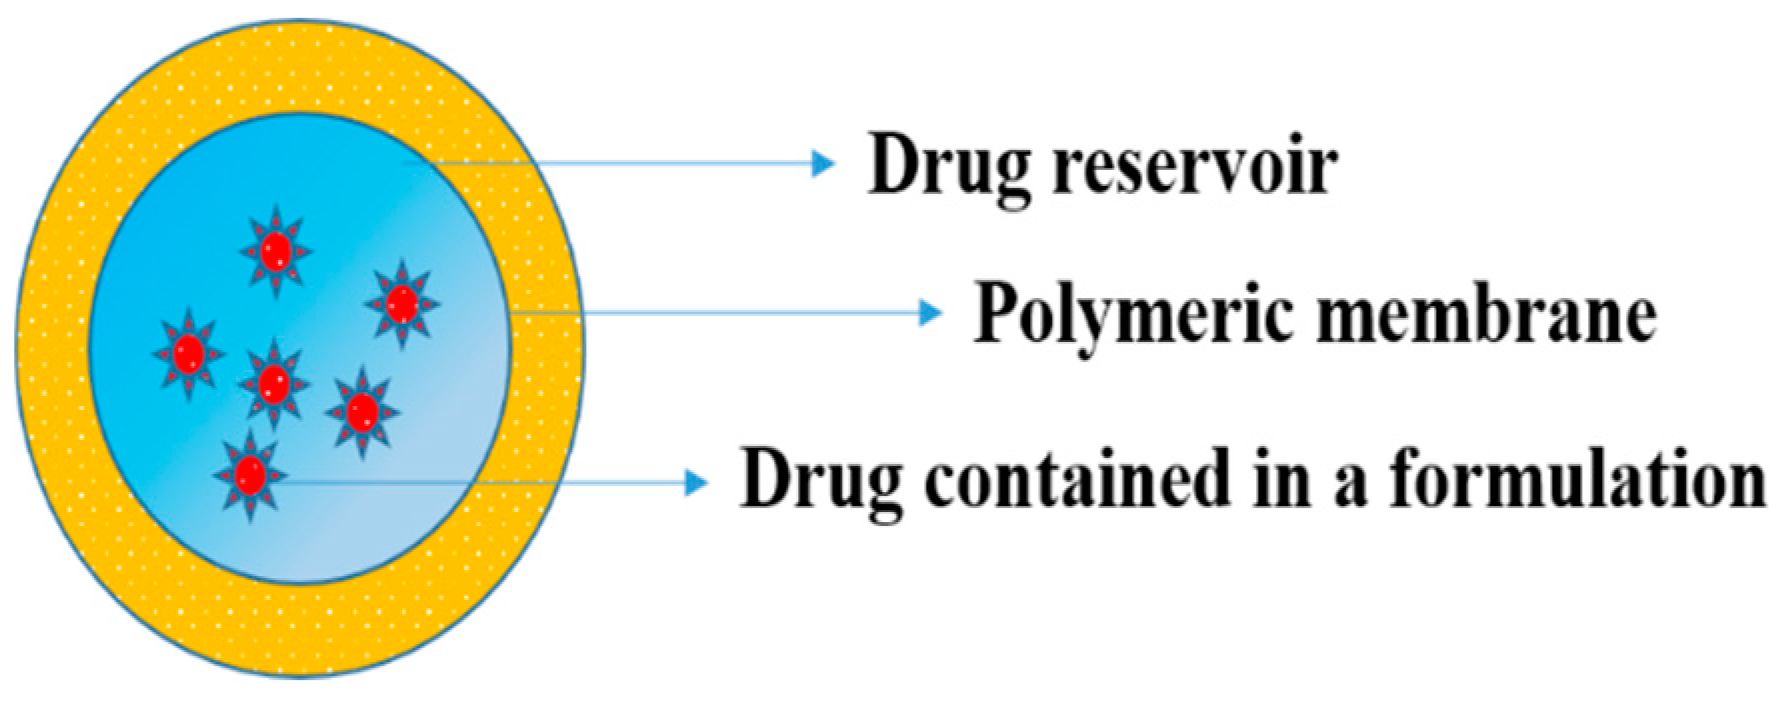

5.2. Drug Delivery by Membranes

5.2.1. Polymeric Membranes

- Yang, W.W.; Pierstorff, E. Reservoir-based polymer drug delivery systems. J. Lab. Autom. 2012, 17, 50–58. [Google Scholar] [CrossRef]